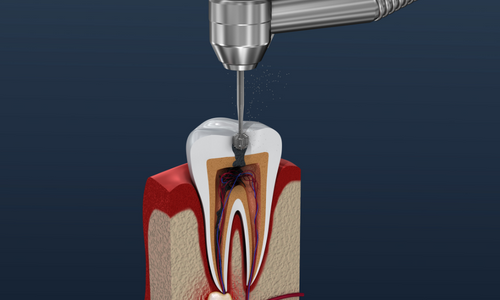

Bununla birlikte, teknolojiye ve yenilikçi uygulamalara verdiğimiz önem de bizi farklı kılan unsurlardan biridir. Tosun Diş

Kliniği olarak, en son diş tedavisi tekniklerini ve ekipmanlarını kullanarak, hastalarımıza en iyi sonuçları sağlamak için

sürekli olarak kendimizi güncelliyoruz. Bu sayede, güvenilir, etkili ve konforlu bir tedavi deneyimi sunarak fark

yaratıyoruz.